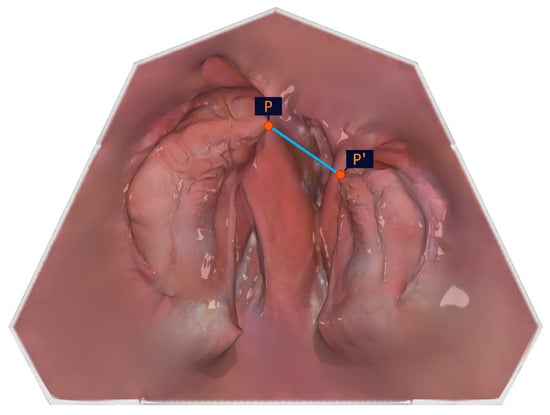

As the cleft edge of the crest of the alveolar ridge (large/small segment; P1/P2) does not represent the shortest distance between the large and the small segments in the pole region, it was important to the authors to include the outermost and foremost points of the alveolar ridge (points P and P′) in the analysis, which describe the closest approach of the segments.

Figure 4. Illustration of the anatomical measuring points. The anatomical measuring points and their description are presented in Table 1.